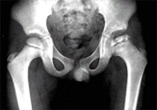

대퇴골의 머리에 해당되는 대퇴골의 골두에

혈액 공급이 되지 않아 엉덩이 관절이 아프면서 다리를 절게 되는 병입니다.

진단은 단순 X-선 촬영만으로도 가능하겠습니다. 다만, 병의 경중을 판단하기 위해서는 전후방 사진 만으로는 부족하고 반드시 측면 사진이 필요합니다. 그러나 방사선 사진에서 확실하지 않은 초기의 환자에서는 방사선 동위 원소 골주사 검사와 자기 공명 영상(MRI)이 도움이 될 수 있습니다.